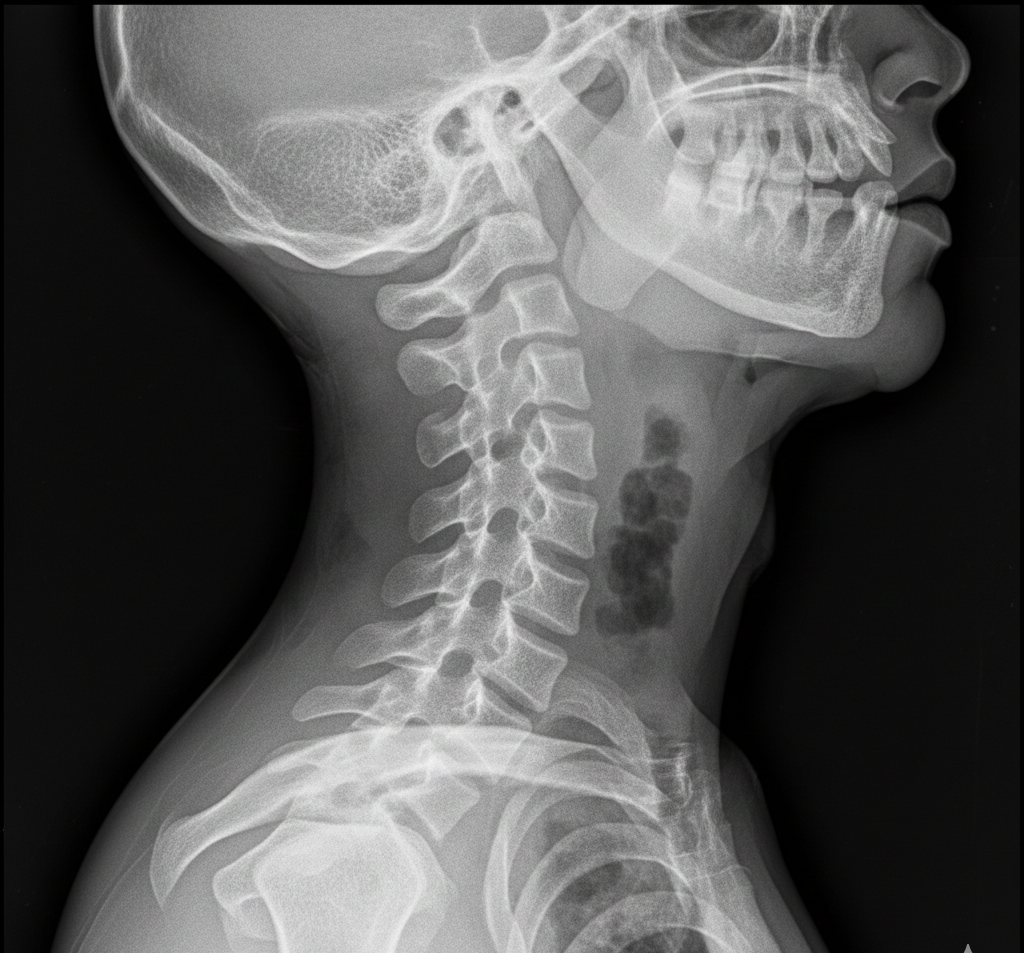

首には、脳へ血液を送る椎骨動脈が通っています。

さらに脊髄が走り、そこから全身へ神経が枝分かれしています。

この部位に強い回旋や過伸展を加えることは、めちゃリスクを伴います。

見えない変形が存在する

多くの方の背骨は、加齢や姿勢不良で変形しています。

骨の端が上下で接触し、仮骨(骨棘)ができることがあります。

これは触診では絶対分かりません。

レントゲンで初めて確認できます。

その状態で強い回旋力を加えれば、骨折のリスクがあります。

頸椎動脈の走行は個人差があります。

椎間関節の角度も違います。

骨棘形成の位置も人それぞれ。

加齢に伴う靭帯の肥厚や石灰化もあります。

見えない情報があまりにも多い。